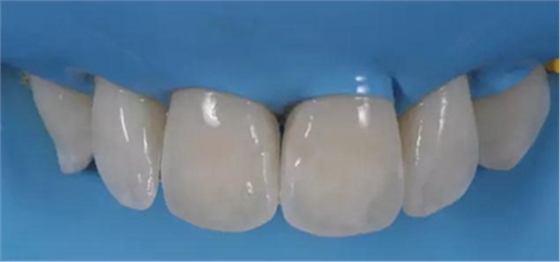

經(jīng)拋光, 治療結(jié)果令人滿意并且印象深刻 (Fig. 7 and 8)。